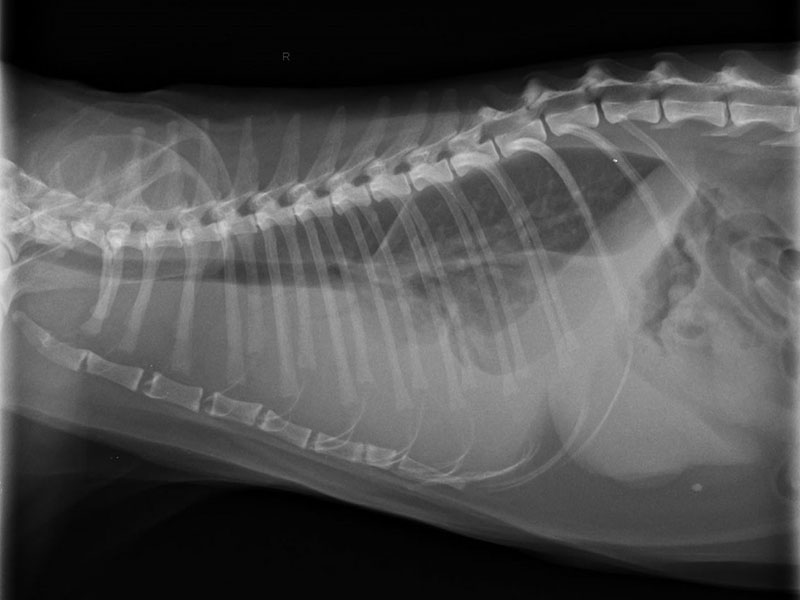

我們曾搶救呼吸困難的毛小孩,經檢查後發現是胸腔積液造成,因狀況緊急,便即刻進行手術,將胸水抽出及供氧處理,經由手術後,毛小孩的生命跡象才逐漸穩定;另一個案,主人形容毛小孩突然倒地,非常虛弱的樣子,我們馬上進行檢查,發現為心包囊積液症狀,經由手術處理後,毛小孩也逐漸恢復元氣。

圖為急診到院,呼吸困難的胸水貓,須立即抽胸水吸氧,穩定生命跡象。